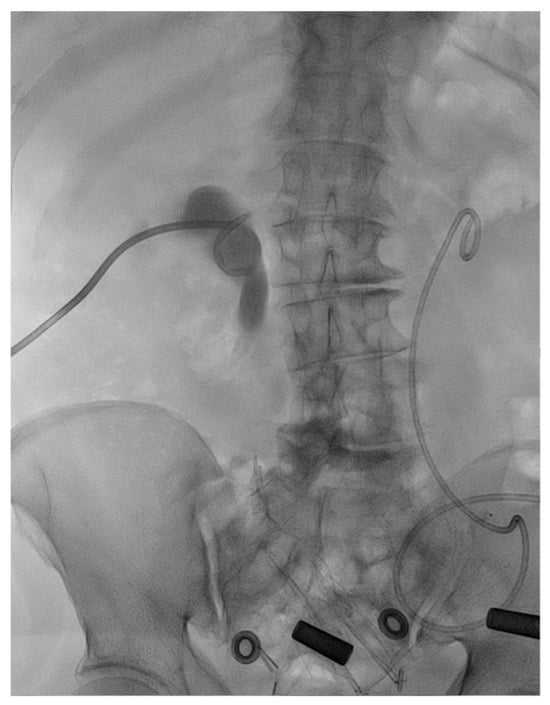

2.2. Treatment

2.3. Outcome and Follow-Up